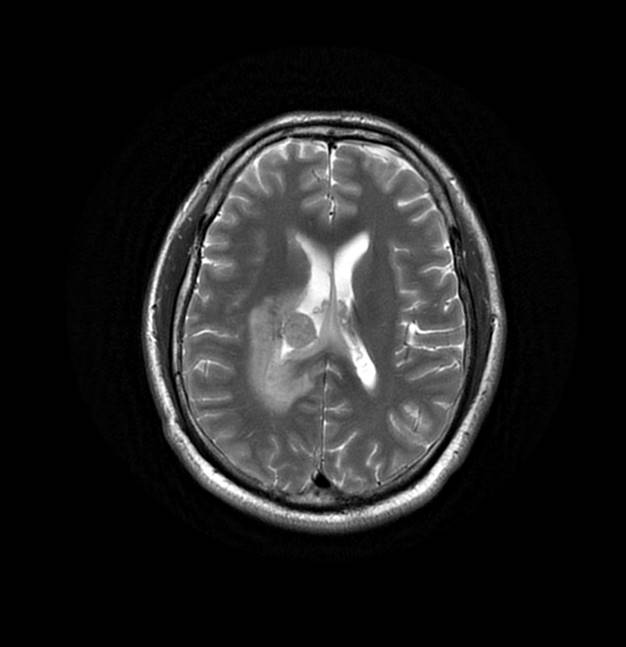

磁共振影像圖

圖2

MR診斷:右側(cè)側(cè)腦室三角區(qū)及側(cè)腦室旁占位,考慮惡性腫瘤可能,間變型腦膜瘤?轉(zhuǎn)移瘤?